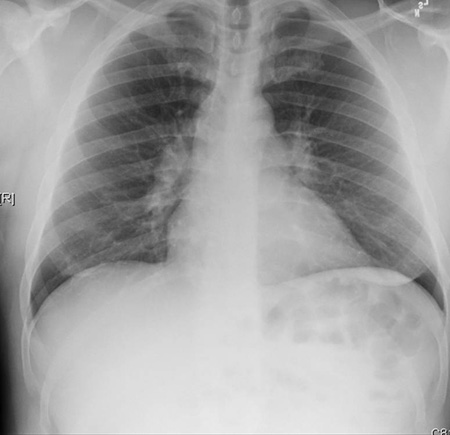

Radiografía de tórax que muestra una adenopatía hiliar bilateral en un paciente con sarcoidosis

De la colección personal del Dr. M.P. Muthiah, Departamento de Medicina Intensiva y Pulmonar y Medicina del Sueño, University of Tennessee